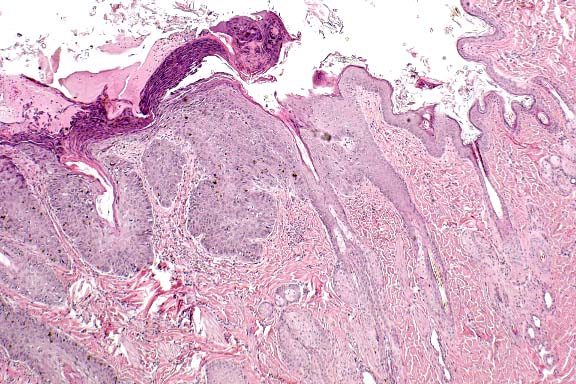

Case 29-1. Skin. Pigmented keratin is distending and distorting hair follicles. The epidermis is also hyperpigmented. The follicles are slanted and the errector pili muscles are parallel to the skin surface. 10X

There is moderate to severe orthokeratotic hyperkeratosis, which extends into the follicular infundibulum with dilation of the follicular ostium. A few catagen and telogen follicles can still be found. The follicular papillum can be identified in abnormal locations, such as adjacent to the sebaceous ducts and at the base of follicles showing severe follicular dilation secondary to keratin accumulation. Some of the hairs are found at very unusual angles. Occasional melanophages are present in the dermis. The sebaceous glands and apocrine glands are within normal limits.

AFIP Diagnosis: Haired skin: Dysplasia, adnexal, with epidermal and follicular orthokeratotic hyperkeratosis, hyperpigmentation, pigmentary incontinence, and follicular dilatation, Chinese Crested, canine.

Conference Note: Additional histologic features of this interesting case were discussed in conference. These include:

a. Arrector pili muscles are often oriented parallel to the skin surface.

b. Apocrine ducts sometimes enter follicles at abnormal locations.

c. Mesenchymal cells of the dermal papillae occasionally surround the epidermal bulb, rather than forming a bulb- or cone-shaped projection surrounded by the hair bulb epidermis.

d. There is remarkable comedo formation.